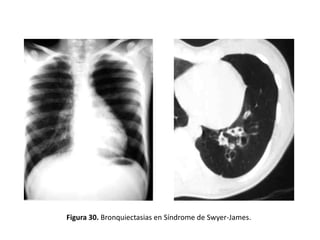

– Síndrome de Swyer-James:

• BQ asociadas a disminución de la vascularización y de la

atenuación pulmonar ipsilateral (Figura 30).

Figura 30. Bronquiectasias en Síndrome de Swyer-James.

Valoración de laextensión de las bronquiectasias y diagnóstico etiológico – Síndrome de Swyer-James: • BQ asociadas a disminución de la vascularización y de la atenuación pulmonar ipsilateral (Figura 30). – Obstrucción bronquial: • Suele dar lugar a BQ localizadas y puede ser: – Intrínseca (estenosis cicatricial, broncolitiasis, cuerpo extraño o tumor) – Extrínseca (adenopatías, tumor, aneurisma) (Figura 31).

Figura 30. Bronquiectasiasen Síndrome de Swyer-James.